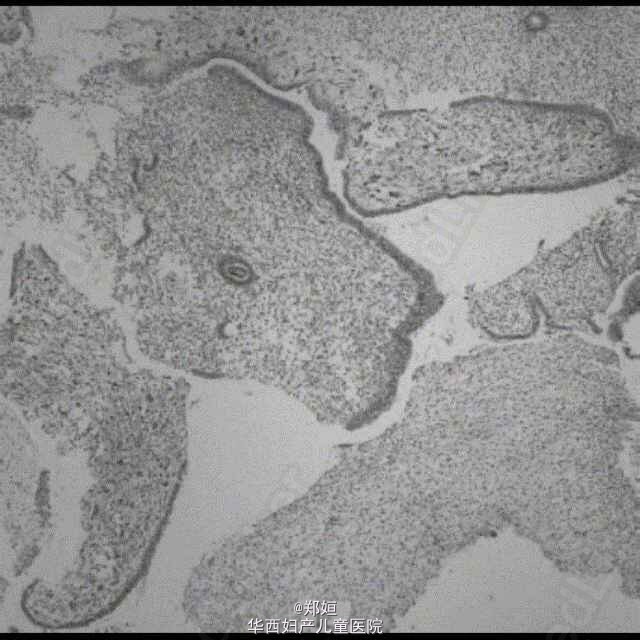

做诊刮,内膜活检提示增生期内膜,可见分散于内膜腺体的不典型子宫内膜基质细胞,部分是多核的,处于上皮层之下。

初步诊断:子宫内膜癌 行全子宫切除

子宫标本提示有一个息肉样的病灶3.5*2.5*2cm,突向子宫腔,切面灰白色 恢复良好